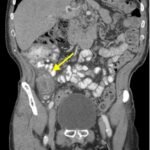

Small bowel diverticulitis is an uncommon subset of acute diverticulitis and can mimic many other intra-abdominal processes. As a result, imaging modalities such as ultrasound and computed tomography (CT) scan are especially important for timely recognition of diverticulitis and can expedite diagnosis and treatment and reduce complications. In the case described in this report, an 81-year-old male with history of esophageal cancer and recurrent diverticulitis with history of multiple bowel resections presented to the emergency department (ED) with right lower quadrant abdominal pain and constipation. Findings on ultrasound were suggestive of diverticulitis, and findings on CT of the abdomen and pelvis showed ileitis with phlegmon and micro-abscess suspicious for small bowel diverticulitis. ED providers should familiarize themselves with ultrasound findings of diverticulitis and be aware that diverticulitis can also present in the small bowel. Treatment of small bowel diverticulitis is similar to colonic diverticulitis.